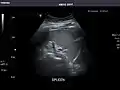

Spleen: Normal in size.

Spleen